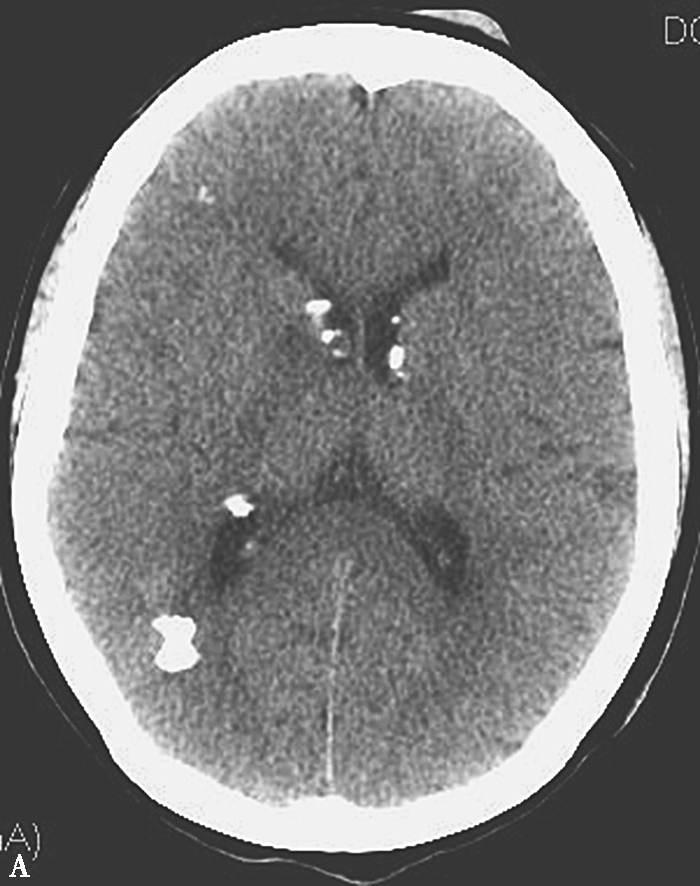

图1-7 结节性硬化

A.CT平扫;B.腰椎矢状位重组,示双侧侧脑室室管膜下、右额叶及右枕叶多发大小不一钙化结节,下胸椎及腰椎椎体内可见类似结节灶